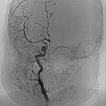

Digital subtraction angiography (DSA) after injection into the right common carotid artery shows the infantile hemangioma mainly supplied from the external carotid artery, as expected.

Digital subtraction angiography (DSA): After insertion of a 4F diagnostic catheter transarterially into the external carotid artery, selective advancement of a microcatheter into the maxillary artery. The infantile hemangioma presents as typical contrast pooling (“tumor blush”). The transvenously inserted balloon blocks the venous outflow and is clearly visible. Embolization was then carried out with particles of 150 micron size and without unintended venous outflow.